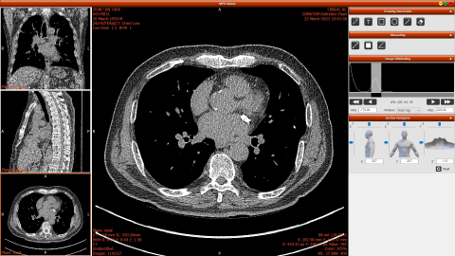

HEXA Pro는 인공지능(AI) 기반 흉부 CT 영상을 자동 분석해 폐, 심장, 간, 갑상선, 유방, 척추 등 주요 장기의 이상 질환을 동시에 탐지하는 차세대 의료영상 솔루션이다.

한 번의 CT 촬영만으로 6개 주요 장기를 분석하며, AI가 병변을 색상으로 표시해 이상 부위를 직관적으로 확인할 수 있다.

분석 결과는 전자문서 리포트(PDF)와 3D 이미지 형태로 제공되어 의료진이 환자의 상태를 한눈에 파악할 수 있으며, PACS 시스템과 연동되어 진료 현장에서 즉시 활용할 수 있다.

이번 전시에서는 병원 도입 사례와 HEXA Pro의 AI 분석 결과 리포트, 3D 시각화 이미지 등이 함께 전시되어, 방문객들이 HEXA Pro의 정확성과 효율성을 직접 확인할 수 있다.